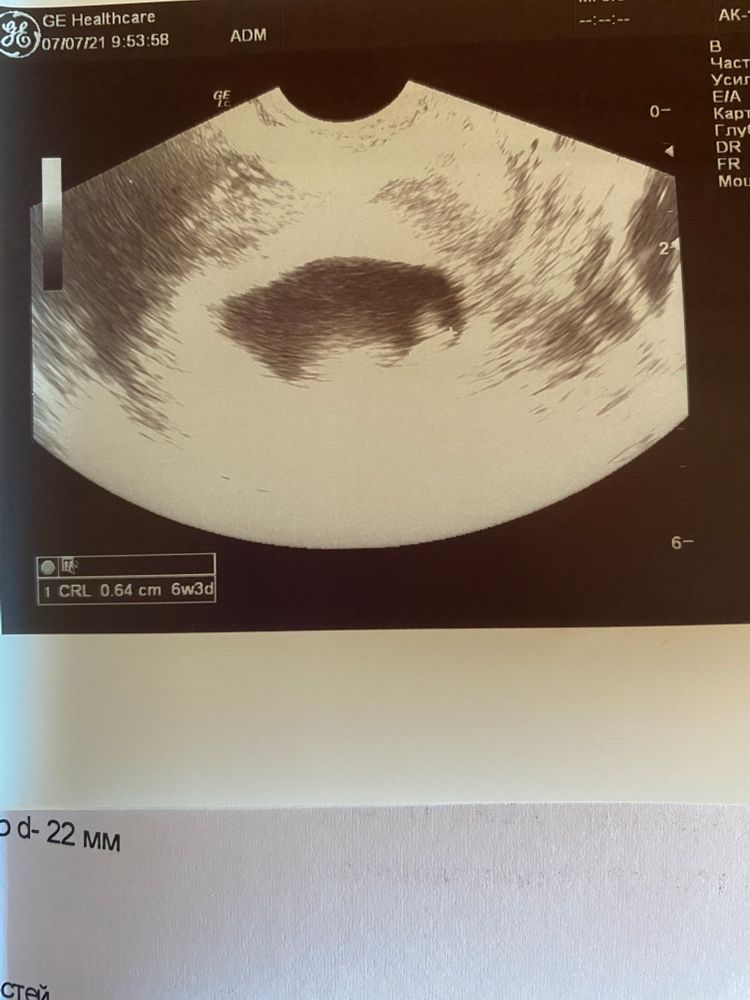

28 дпп 07.07.2021 - второе узи: малыш наконец-то показался - ПЯ 28мм, ктр 6,4мм, что соответствует сроку 6 недель 3 дня, сердцебиение регистрируется, жм 4,5 мм.